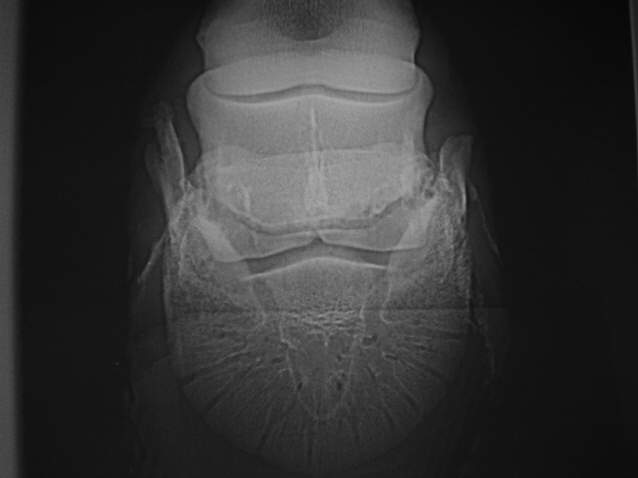

Starke Zubildungen und Umbauvorgänge am oberen und unteren Rand (nicht frakturiert)